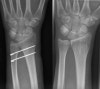

손목에서 상당한 척골 양성 변이(positive ulnar variance)가 관찰됩니다(7mm 이상의 척골 양성 변이 : 골간막의 완전 파열과 요골의 근위 전위를 의미).

X-ray : 전완부 골간막 손상(Essex-Lopresti injury)

수술적 치료방법으로 요골길이의 재건 및 원위요척관절(DRUJ)의 안정성 회복을 도모합니다.

원위 요척관절과 요골두 수술후 3~5일간 장 상지 석고 부목(long arm splint)으로 안정합니다.